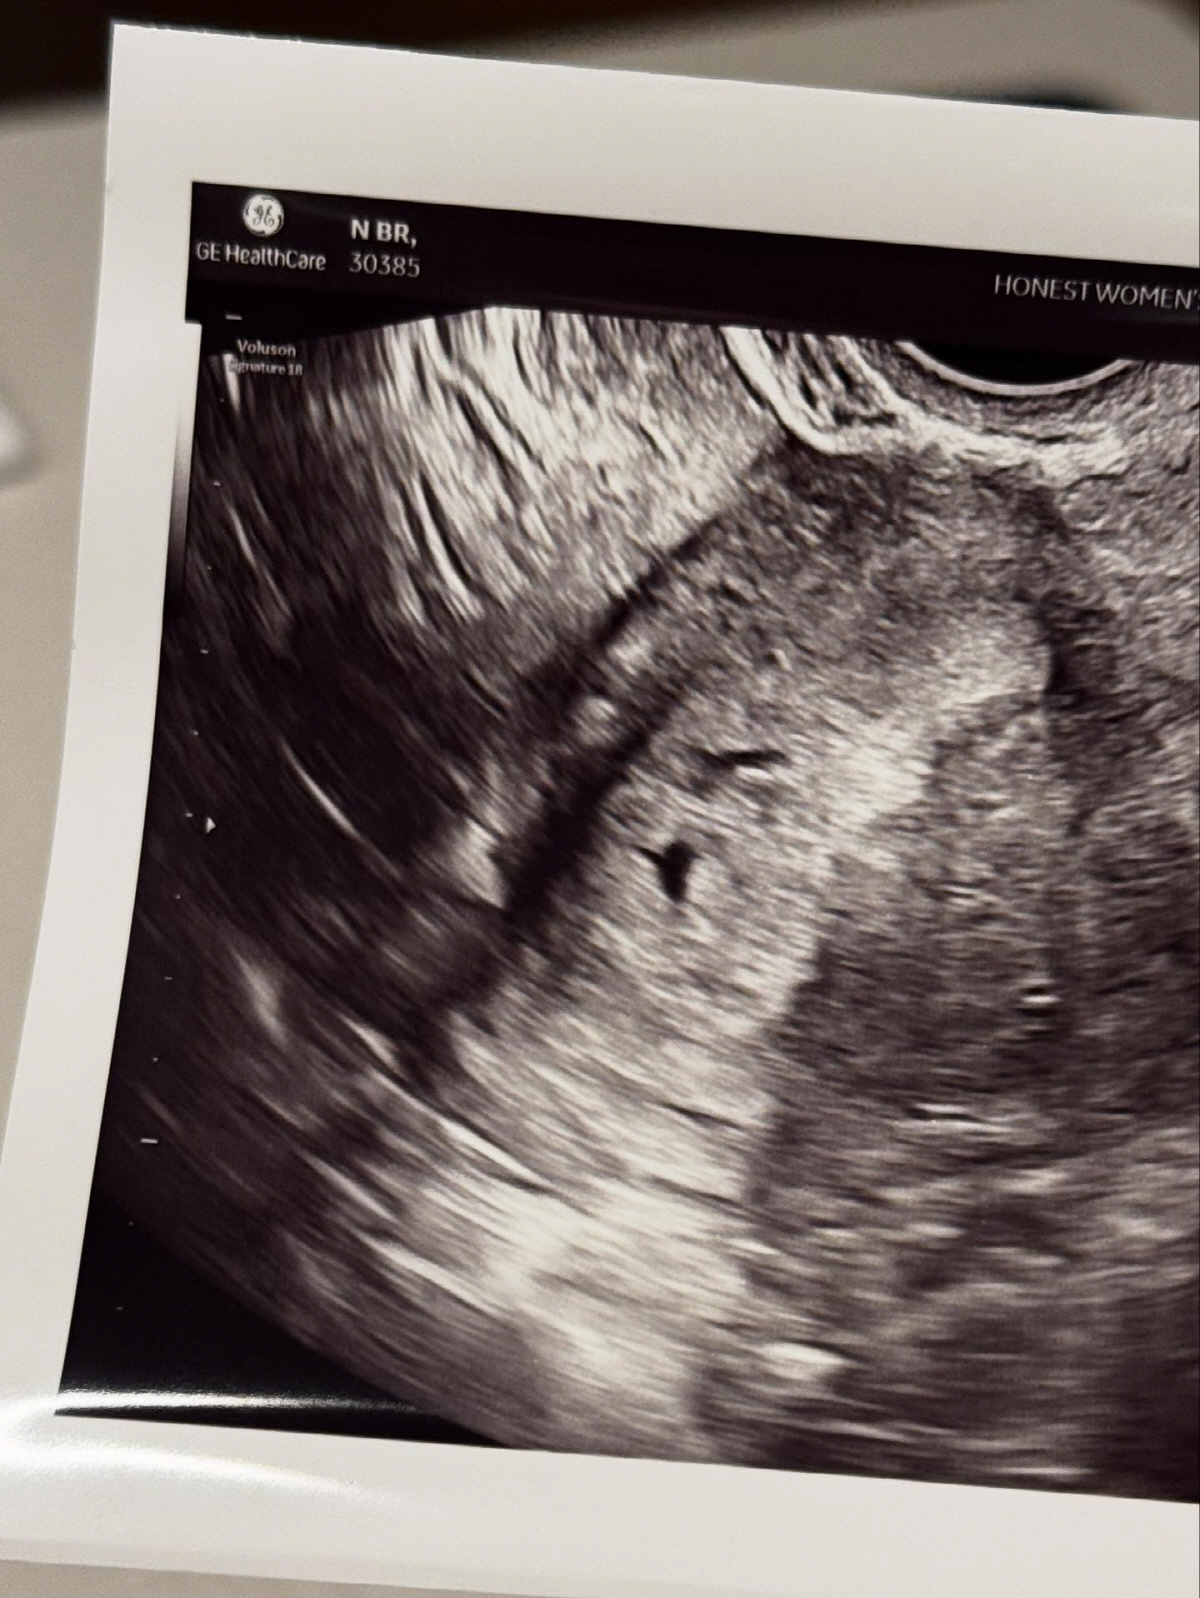

앞서 지난 11일 남보라는 "새 생명이 찾아왔다. 곧 엄마가 된다"면서 임신 소식을 전했다.

출산 예정일은 내년 6월 중순으로 현재 임신 현재 12주차인 남보라는 "올해 안에는 임신을 하고 싶었는데 너무 감사하게 적절한 시기에 찾아와줘서 요즘 매일 행복한 시간을 보내고 있다. 뱃속에서 건강하게 잘 키워서 새 가족 맞을 준비를 잘 해보겠다"며 임신 소감을 전했다.